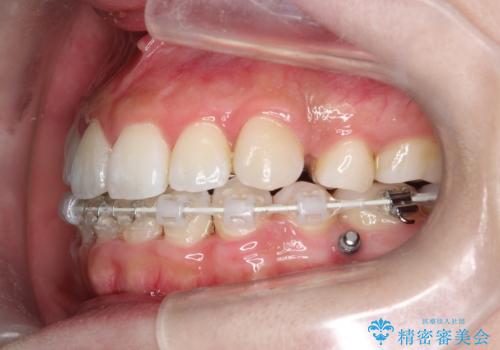

八重歯を改善!美しい口元を実現するハーフリンガル矯正

- 矯正装置

- ハーフリンガル

- 前歯のガタツキと口元のコンプレックスを解消するために来院されました。

ハーフリンガルワイヤー矯正で治療を開始しました。

ハーフリンガル矯正は、見た目を気にせずに矯正治療ができる方法です。この治療法は、八重歯や前歯のガタツキを効果的に改善します。特徴として、ワイヤーが上の歯の裏側に装着されるため、装置が外から見えません。これにより、治療中も自然な笑顔を保ちながら安心して治療を続けることができます。歯並びの悩みを持つ方にとって、非常に魅力的な選択肢です。